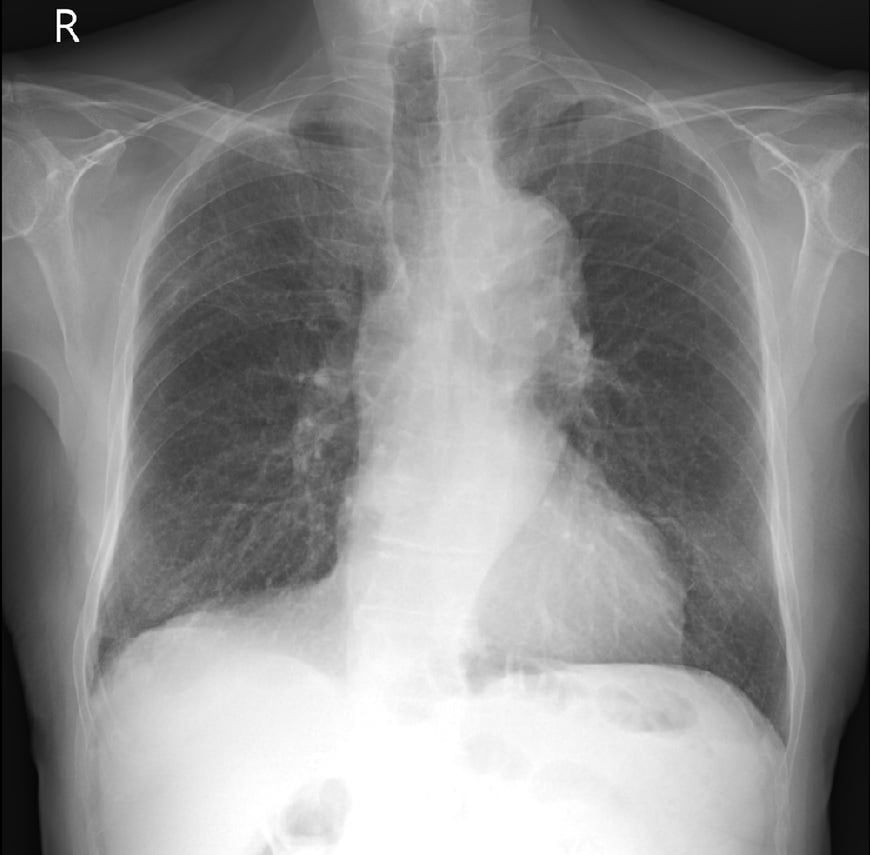

Rezydent opublikował dwie fotografie RTG, które były wykonane u jednego chorego z pozytywnym wynikiem na koronawirusa. "Pierwsze RTG wykonano przy przyjęciu do szpitala, u pacjenta dodatniego z osłabieniem i gorączką, jeszcze bez duszności. Drugie wykonano u tego samego chorego po 7 dniach hospitalizacji, już w skrajnej niewydolności oddechowej wymagającej respiratoroterapii" - opisuje lekarz.

Obraz płuc przed wystąpieniem duszności

Obraz płuc przed wystąpieniem duszności © Tomasz-Rezydent

Wyjaśnia, że ciemnie obszary płuca na pierwszym zdjęciu są w większości z niezmienionej jeszcze chorobowo tkanki, natomiast nakrapiane mlecznie płuca są praktycznie w całości zajęte (odpowiadają 80 proc. zajętego miąższu w tomografii komputerowej).